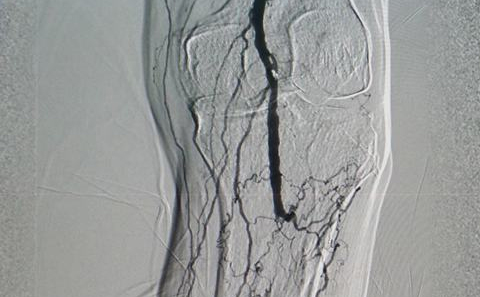

Bung dù thông liên nhĩ và can thiệp mở tắc gây hẹp động mạch chi bằng máy DSA (Ảnh: Bội Nhiên)